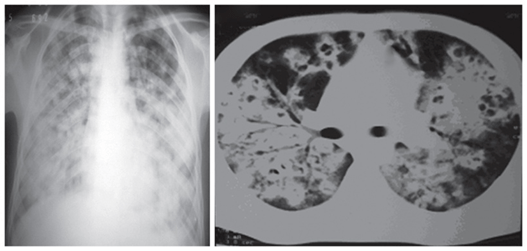

肺球孢子菌病